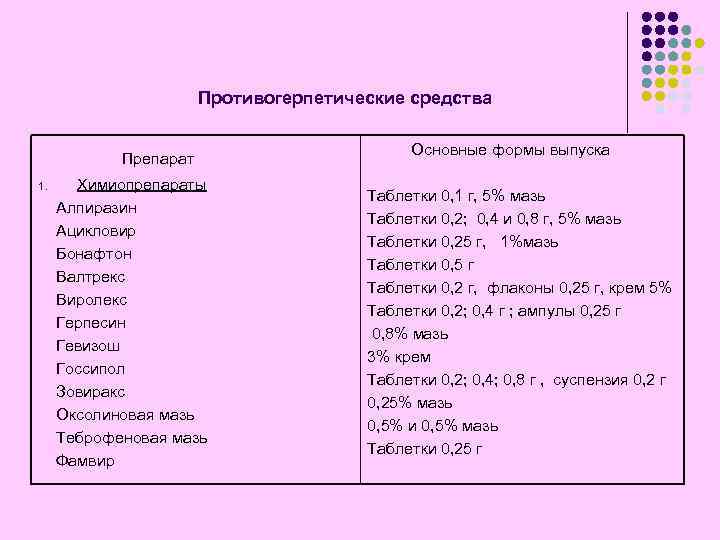

Противогерпетические средства Препарат 1. Химиопрепараты Алпиразин Ацикловир Бонафтон Валтрекс Виролекс Герпесин Гевизош Госсипол Зовиракс Оксолиновая мазь Теброфеновая мазь Фамвир Основные формы выпуска Таблетки 0, 1 г, 5% мазь Таблетки 0, 2; 0, 4 и 0, 8 г, 5% мазь Таблетки 0, 25 г, 1%мазь Таблетки 0, 5 г Таблетки 0, 2 г, флаконы 0, 25 г, крем 5% Таблетки 0, 2; 0, 4 г ; ампулы 0, 25 г 0, 8% мазь 3% крем Таблетки 0, 2; 0, 4; 0, 8 г , суспензия 0, 2 г 0, 25% мазь 0, 5% и 0, 5% мазь Таблетки 0, 25 г

Противогерпетические средства Препарат 1. Химиопрепараты Алпиразин Ацикловир Бонафтон Валтрекс Виролекс Герпесин Гевизош Госсипол Зовиракс Оксолиновая мазь Теброфеновая мазь Фамвир Основные формы выпуска Таблетки 0, 1 г, 5% мазь Таблетки 0, 2; 0, 4 и 0, 8 г, 5% мазь Таблетки 0, 25 г, 1%мазь Таблетки 0, 5 г Таблетки 0, 2 г, флаконы 0, 25 г, крем 5% Таблетки 0, 2; 0, 4 г ; ампулы 0, 25 г 0, 8% мазь 3% крем Таблетки 0, 2; 0, 4; 0, 8 г , суспензия 0, 2 г 0, 25% мазь 0, 5% и 0, 5% мазь Таблетки 0, 25 г